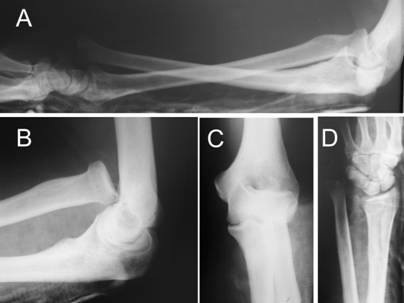

The injury was treated immediately, with closed reduction of both dislocations, K-wire stabilization of the DRUJ and immobilization of the forearm with a long arm cast in supination. Under general anaesthesia firstly the radial head was reduced with traction, supination and direct pressure, followed by reduction of the DRUJ with pronation, while the reduced radial head was maintained in supination by an assistant. After the reduction, the radial head was unstable whenever the forearm was positioned in neutral rotation. Therefore it was decided to stabilise the DRUJ with a K-wire in the reduced position and immobilise the forearm with a long arm cast in supination and the elbow in 90 degrees flexion [Fig.2].

Post-operative lateral radiograph of the forearm (A) and anterior-posterior radiograph of the wrist (B).

Although an increase in the distance at the DRUJ was observed on AP view (figure 2), the reduction was accepted. In fact, a perfect reduction was not achieved. It would be interesting to see if this would have caused problems in the patient's wrist after some period of time. Unfortunately we were able to follow-up the patient only for three months post-operatively.